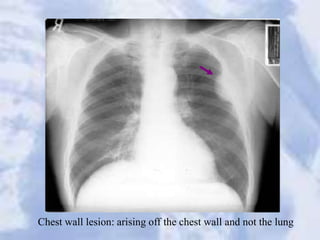

Chest wall lesion: arising off the chest wall and not the lung

Chest wall lesion:arising off the chest wall and not the lung